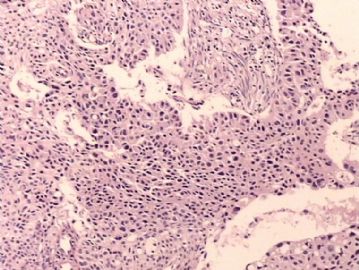

腺鳞癌?

姓    名: ××× 性别:   年龄:  39岁

标本名称:  宫颈活检

简要病史:  同房出血3次,tct HSIL

考虑:原位腺癌,小灶性区域有鳞状上皮向间质内浸润,考虑有鳞状细胞癌结构。

• 腺鳞癌?图2

图2